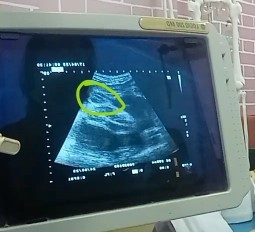

หมอไม่แน่ใจว่าเพศอะไร น้องจะเป็นหญิงหรือชายคะ ตอนนี้20weekแล้วค่ะ

ญ ค่ะ ของเราก็แบบนี้ ซาวดูเพศซ้ำ3-5รอบ เพื่อความชัว กรีบลูกสาวใหญ่มาก🤣

คิดว่าน่าจะผญค่ะแม่ ไม่มีพวงอัณฑะเลย 😄

น่าจะผู้หญิงนะคะแม่

ผู้หญิงแน่นอนค่ะ